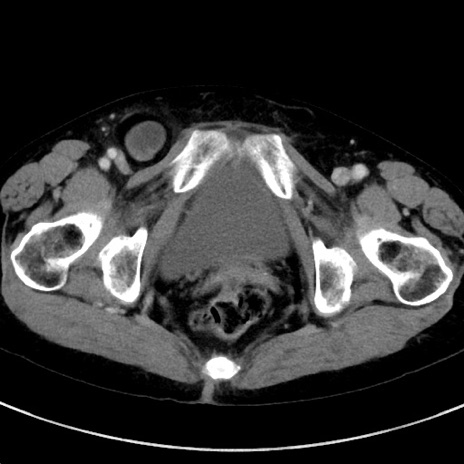

症例23(横断像)

【症例】70歳代女性

【主訴】下腹部痛・嘔吐

【現病歴】2日前より腹痛あり。昨日嘔吐あり。症状改善しないため来院。

【既往歴】胃GISTに対して胃部分切除後。

【身体所見】BT 37.1℃、BP 128/77mmHg、腹部:平坦・軟、下腹部に圧痛あり。

【データ】WBC 10200、CRP 0.31